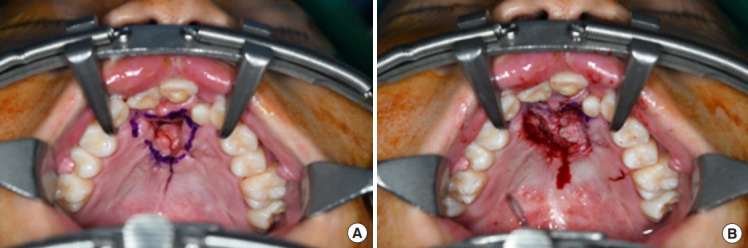

The ultimate goal of cleft palate repair is to achieve an intact palate with the separation of the oral and nasal cavities. However, some patients develop an oronasal fistula in the secondary palate after palatoplasty. Postoperatively, a secondary palatal oronasal fistula may develop, leading to functional problems. In this study, we describe a patient with recurrent oronasal fistula and alveolar cleft with multiple failed previous reconstructions at another clinic. The oronasal fistula and alveolar cleft were repaired using a tongue flap and an iliac bone graft, respectively. The patient demonstrated excellent clinical progress with no recurrence of the oronasal fistula at the 1-year follow-up.